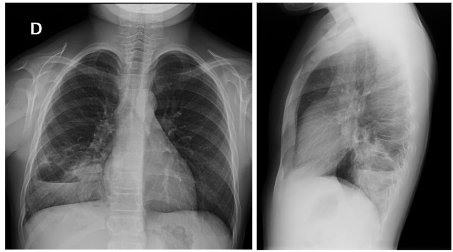

Traditionally, CPMs were diagnosed in the neonatal or postnatal period using chest radiography (Figure 1) or computed tomography (CT) in newborns with unexplained respiratory distress, or in children with recurrent respiratory infections. In other cases, they were incidentally discovered during imaging performed for unrelated reasons.

Figure 2. Congenital pulmonary malformations with large and small cystic areas of hyperinflation. No systemic irrigation was observed.

In the postnatal period, the gold standard remains contrast-enhanced computed tomography (CT angiography), which enables high-resolution evaluation of the bronchial tree integrity, characterization of parenchymal architecture (Figure 4), and assessment of the number and size of cysts (Figure 2). It also allows for precise visualization of aberrant systemic vessels (Figure 5), as well as evaluating compressive effects on mediastinal structures.